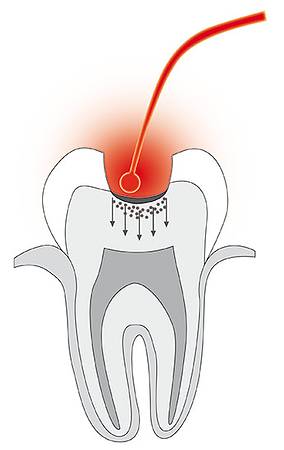

- Kariestherapie

- Kariestherapie

© Cumdente